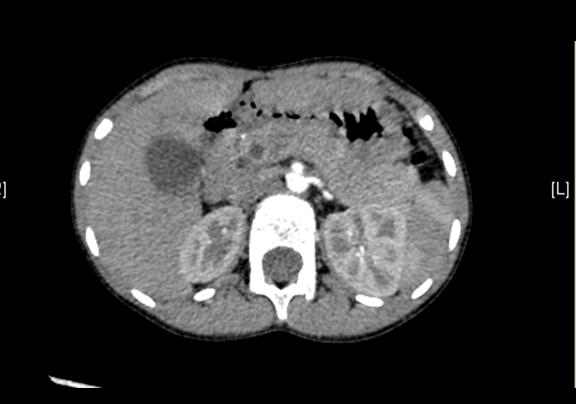

上腹部CT平扫:先天性胆管囊状扩张症并胆囊结石、胆囊炎症。

上腹部增强CT:肝总管-胆总管中上段梭形增宽,符合先天性胆管扩张所见(Ⅰ型)。

术前CT检查:

动脉期

静脉期

平衡期